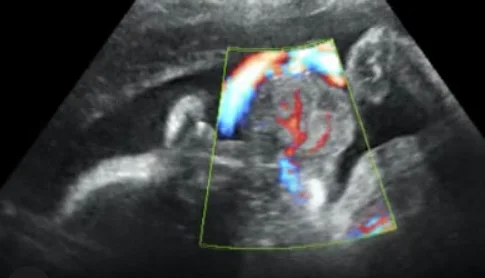

U quái vùng hầu họng thai (Epignathus)